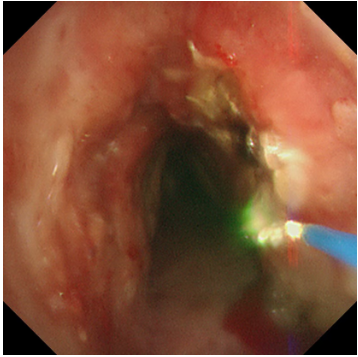

冷凍修復(fù),深度“清創(chuàng)”:隨后,應(yīng)用冷凍探頭對(duì)殘余的增生組織及基底進(jìn)行凍融治療。極低溫的探頭接觸組織,能使其變性、壞死并最終脫落,同時(shí)還能有效止血、減少瘢痕形成。這一步驟如同為氣道進(jìn)行一次深度的“保養(yǎng)與清潔”,能更徹底地清除病灶,降低復(fù)發(fā)風(fēng)險(xiǎn)。

兩種技術(shù)優(yōu)勢(shì)互補(bǔ),相得益彰,在微小創(chuàng)傷的前提下,實(shí)現(xiàn)了對(duì)復(fù)雜氣道狹窄的最大化疏通。